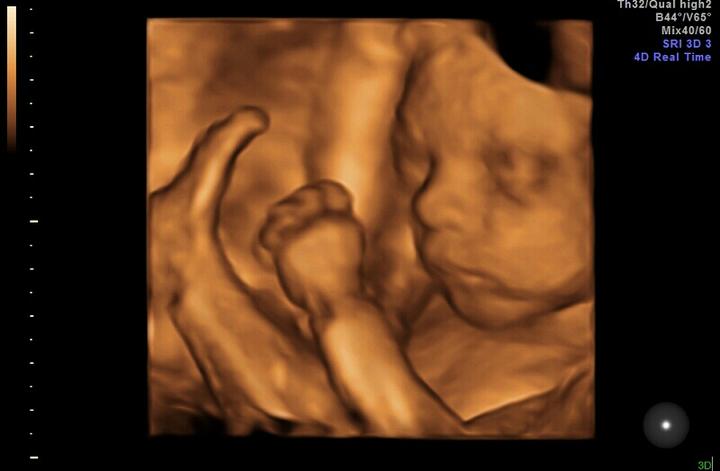

Prosim vas baby ktore ste mali nizko polozeni placentu rodili ste priodzene?popravilo sa vam to?mne bol nariadeny klud